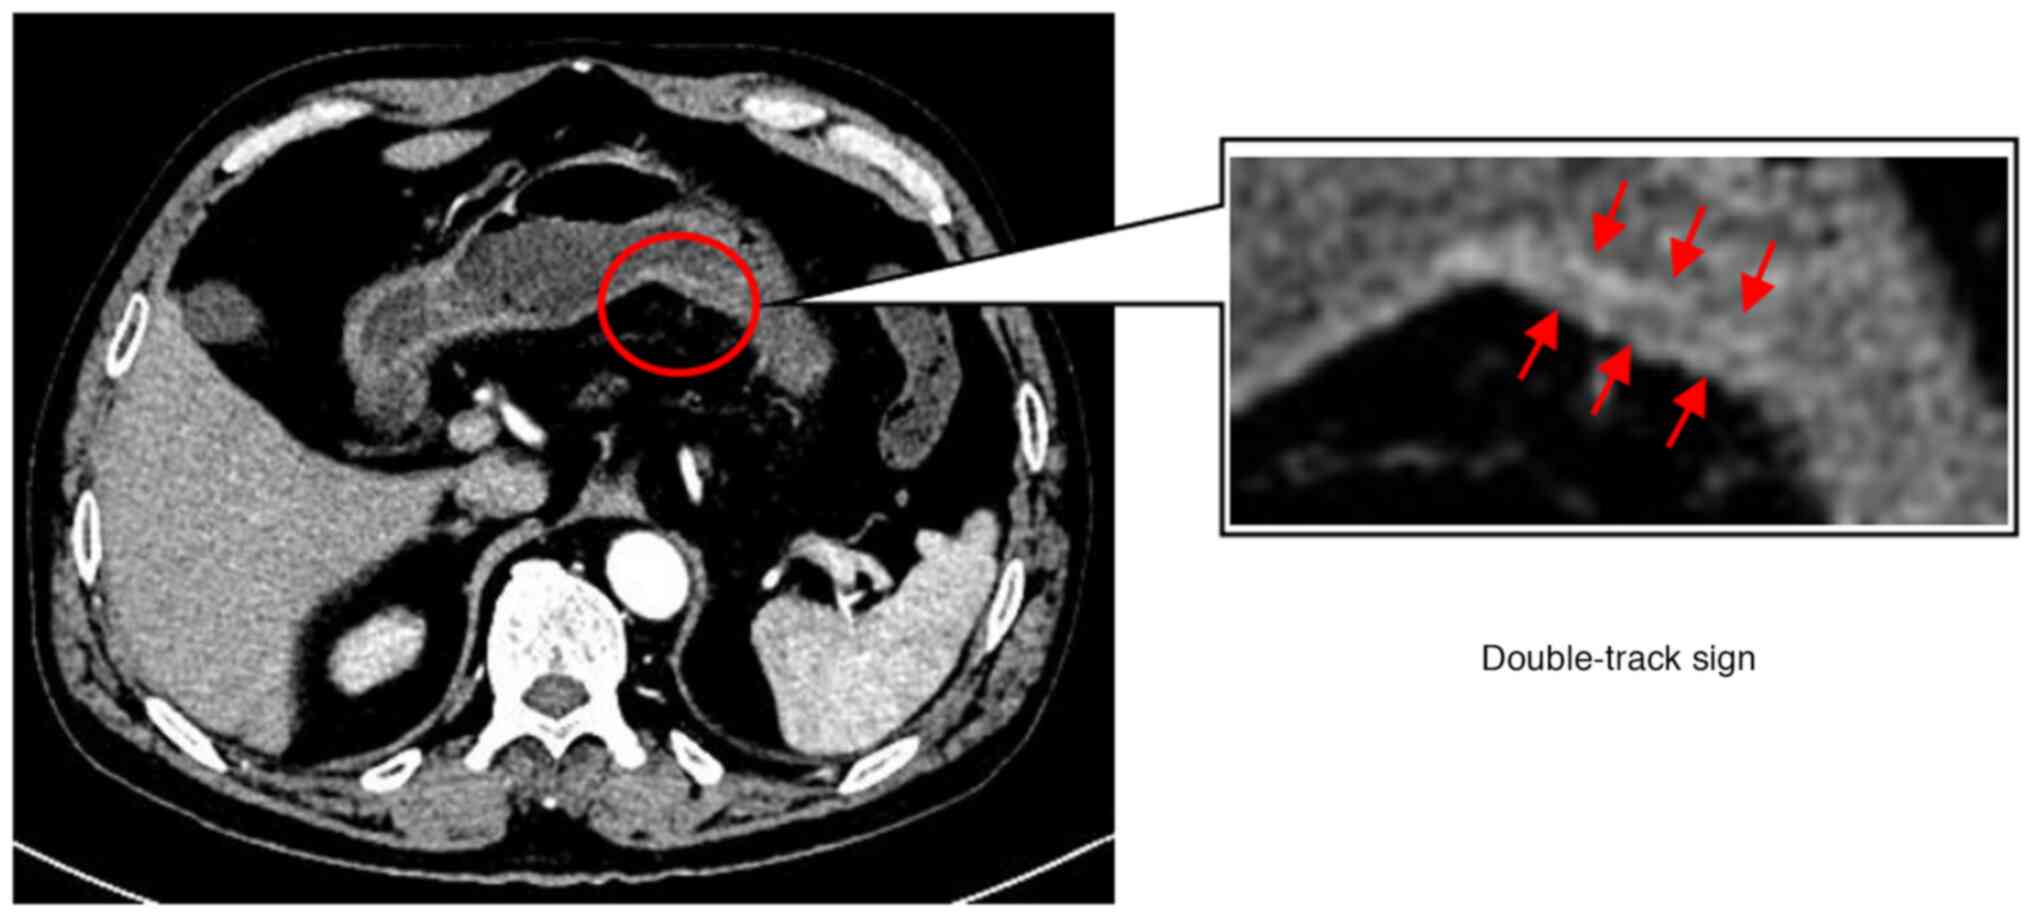

The ‘double‑track sign’: A novel CT finding suggestive of the diagnosis of T1a gastric cancer

Effective identification of T1a stage cancer is crucial for planning endoscopic resection for early gastric cancers. The present study aimed to determine the diagnostic value of the double‑track sign in patients with T1a gastric cancer using computed tomography (CT) imaging. A total of 152 patients diagnosed with pathologically proven T1a gastric cancer at The First Affiliated Hospital of Zhengzhou University (Zhengzhou, China) between July 2011 and August 2021 were retrospectively reviewed. The control group consisted of 2,926 patients with gastritis. Clinical data, including patient characteristics and preoperative CT imaging findings with gastric morphological features, were reviewed and analyzed. Out of 51 patients with T1a gastric cancer finally included, 31 (60.8%) exhibited local double‑track enhancement changes of the stomach, referred to as the ‘double‑track sign’, on CT images. In addition, four patients (7.8%) had well‑enhanced mucosal thickening of the gastric wall. Of the 2,926 control subjects, none had any double‑track sign and six patients (0.2%) had local gastric wall thickening with abnormally strengthened enhancement. In conclusion, a double‑track sign on CT images is beneficial in the diagnostic differentiation of T1a gastric cancer.